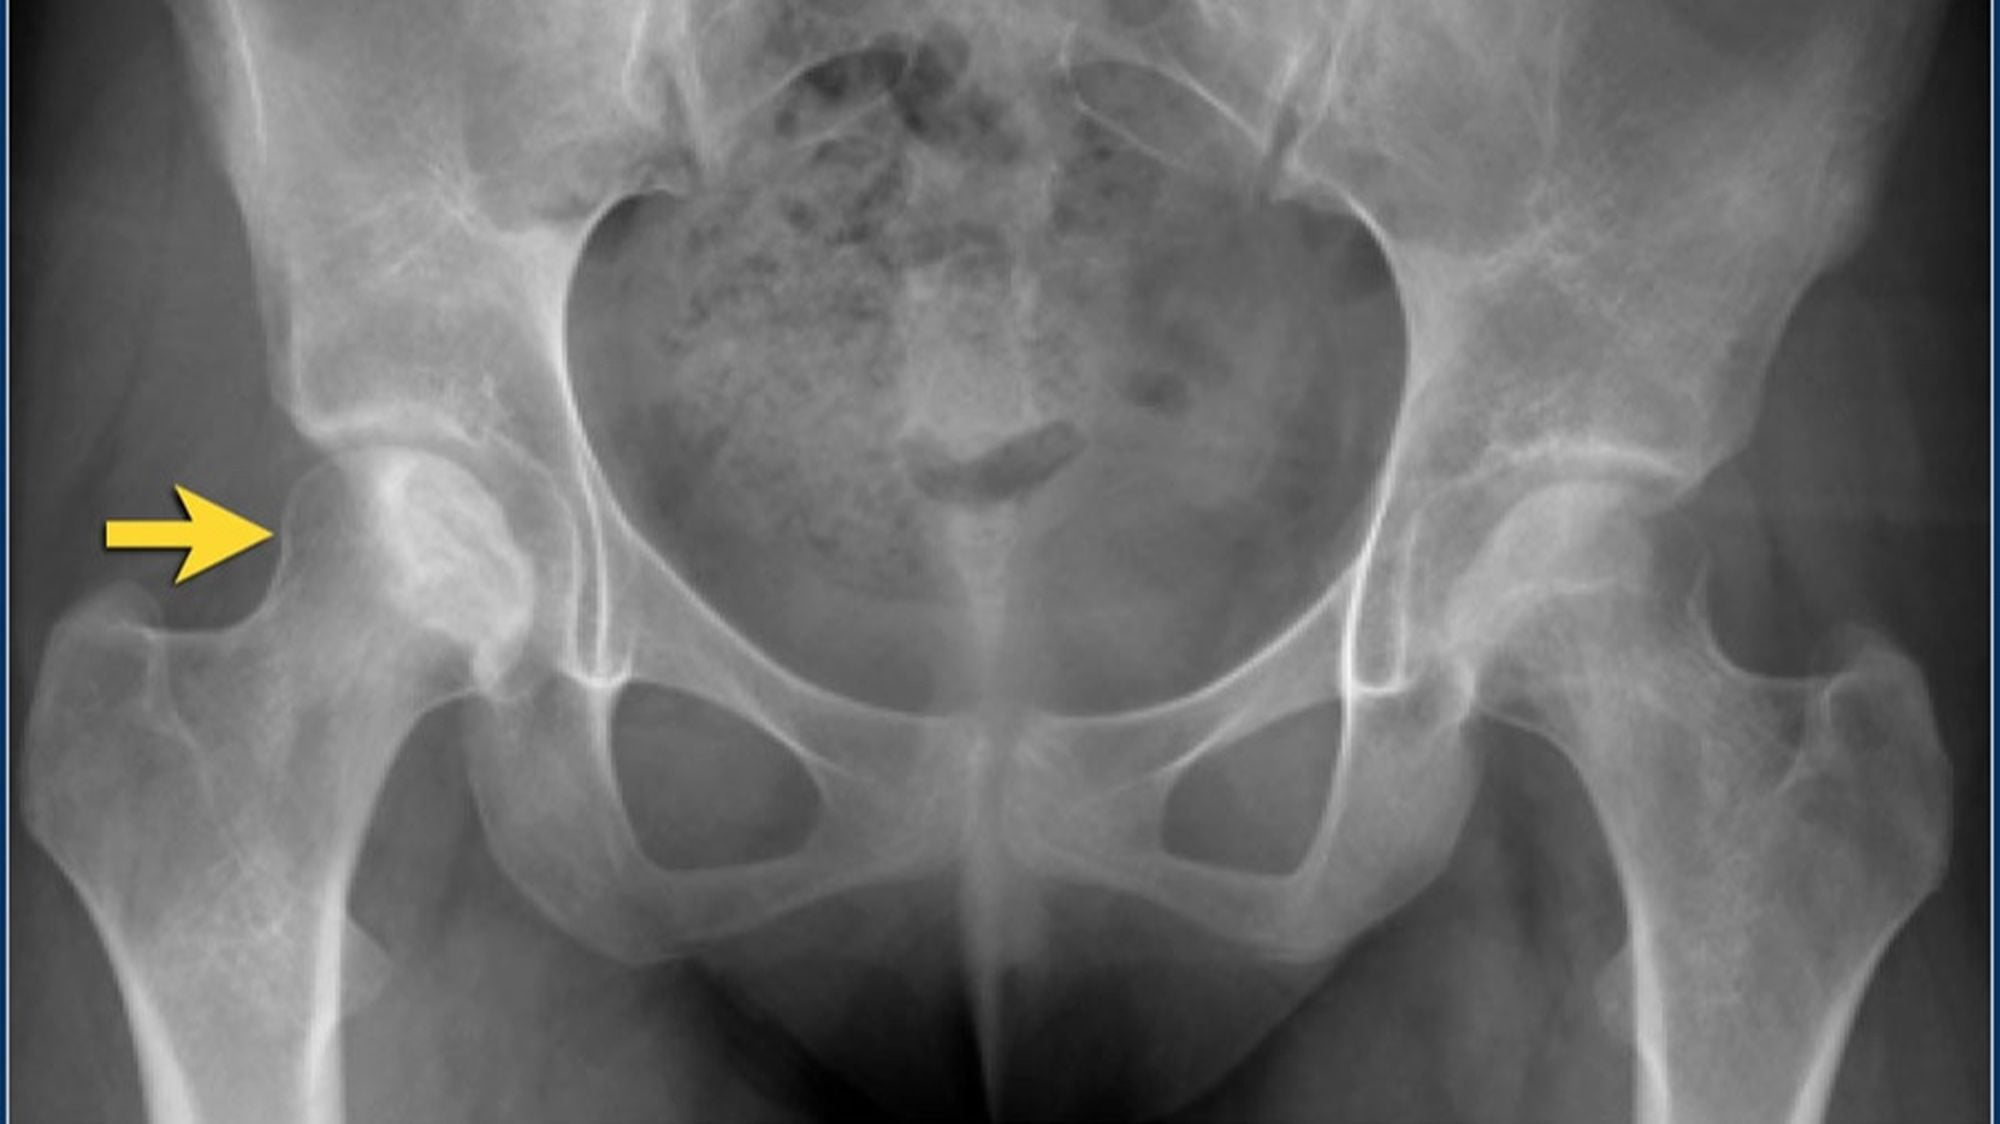

Radyografi

Avasküler Nekroz'un erken evrelerinde düz radyografik bulgular dikkat çekici değildir. Bununla birlikte, Amerikan Radyoloji Koleji, kalça ağrısı ile başvuran Avasküler Nekroz riski taşıyan hastalarda pelvis röntgenini en uygun başlangıç görüntüleme çalışması olarak görmektedir. Bu projeksiyonlardan sadece birinde eklem çökmesi veya kortikal çöküntü görülebileceğinden, hem pelvisin ön-arka görünümü hem de kalçanın kurbağa bacağı lateral görünümü gereklidir.

Hafif-orta Avasküler Nekroz'da radyografiler skleroz ve kemik yoğunluğundaki değişiklikleri gösterir. İlerlemiş hastalıkta düzleşme, subkondral radyolüsent çizgiler (hilal işareti) ve femur başının çökmesi gibi kemik deformiteleri belirgindir.

Evreleme

Birkaç farklı evreleme sistemi geliştirilmiş ve kullanılmaya devam etmektedir. En önemli husus femur başı korteksinin çökmesidir. Çökmeden önce onarım ve tam kurtarma mümkün olabilir. Daha sonra, çöküş geri döndürülemez. Uluslararası Kemik Dolaşımı ve Kemik Nekrozu Birliği Adlandırma Alt Komitesinin fikir birliğine dayanan evreleme sistemi şu şekildedir:

- Radyografik bulgular subkondral lusensi (hilal işareti) ve subkondral çökmeyi içerir,

- Femur başının şekli genellikle radyografilerde ve BT taramalarında korunur.

- Femur başında düzleşme veya çökme mevcuttur,

- Eklem boşluğu düzensiz olabilir,